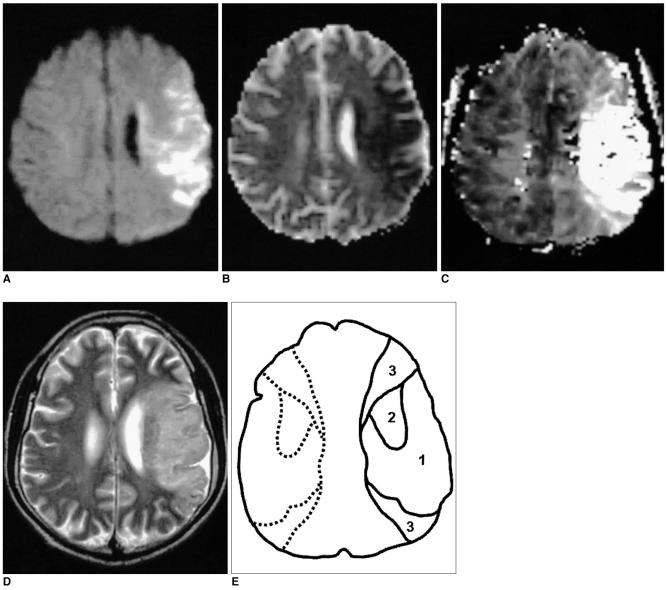

MATERIALS AND METHODS

Both DWI and PWI were performed within six hours from the onset of symptoms for 12 patients who had suffered from acute stroke. Three regions of interest (ROIs) were identified: ROI 1 was the initial lesion on DWI; ROI 2 was the DWI/PWI mismatch area (the penumbra) that progressed onward to the infarct; and ROI 3 was the mismatch area that recovered to normal on the follow-up scans. The ratios of apparent diffusion coefficient (ADC), the relative cerebral blood volume (rCBV), and the time to peak (TTP) were calculated as the lesions' ROIs divided by the contralateral mirror ROIs, and these values were then correlated with each other. The viability threshold was determined by using the receiver operating characteristic (ROC) curves.

材料与方法

对12例急性脑卒中患者在症状发作后6小时内进行DWI和PWI检查。确定了三个感兴趣区域(ROI):ROI 1是DWI上的初始病变;ROI 2是DWI/PWI不匹配区域(半暗带),该区域随后进展为梗死;ROI 3是在随访扫描中恢复正常的不匹配区域。表观扩散系数(ADC)、相对脑血容量(rCBV)和达峰时间(TTP)的比值通过将病变的ROI除以对侧镜像ROI来计算,然后将这些值相互关联。使用受试者操作特征(ROC)曲线确定存活阈值。